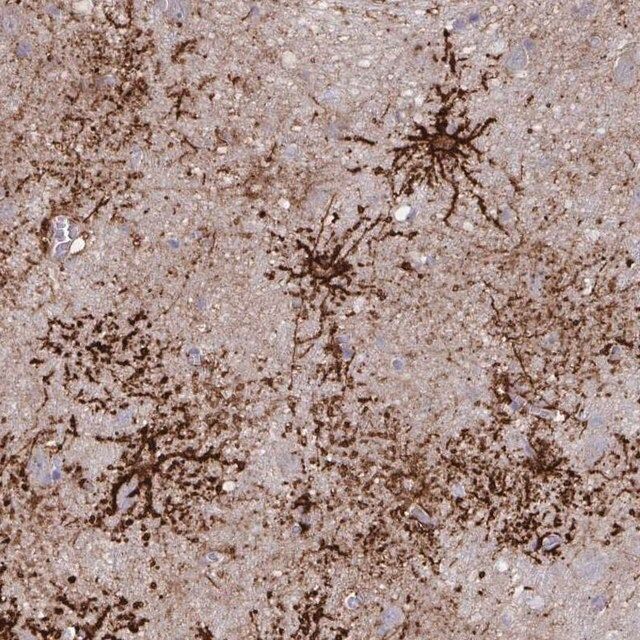

水通道蛋白 4 (aquaporin 4,AQP4) 是一种内源性蛋白,属于水通道蛋白家族,由 13 个成员组成。该基因位于人类 18 号染色体 q11-q12,有 4 个外显子和 3 个内含子。编码的蛋白有 5 个环,由 6 个跨膜结构域干预。环 A、C 和 E 面向浆外区,环 B 和 D 存在于胞浆区。在肺、胃和肾等外周器官中表达。是中枢神经系统表达的主要水通道。它由星形胶质细胞表达,并优先定位于星形胶质细胞的终足突起。它以两种可变剪接形式存在— 长的称为 M1,短的称为 M23。

人类蛋白质图谱项目可细分为三个方面的工作:人类组织图谱、癌症图谱和人类细胞图谱。支持 Tissue and Cancer Atlas 项目而产生的抗体,已经通过免疫组化针对数百个正常和疾病组织进行了测试,通过 Human Cell Atlas 项目最近的努力,很多已经通过免疫荧光法进行了表征,不仅在组织级别,现在也在亚细胞级别绘制了人类蛋白质组图谱。通过点击图像库链接,可以在 Human Protein Atlas (HPA) 位点上查看这些图像和这个庞大数据集的集合。要查看这些协议 和其他有关 Prestige 抗体和 HPA 的有用信息,请访问sigma.com/prestige。

水通道蛋白 4 (aquaporin 4,AQP4) 是脑内主要的水转运体,被认为是维持脑内水分稳态的重要物质。因此,AQP4 可能在脑水肿的发病机制中起重要角色。研究显示,这种转运体在脑缺血中过度表达。因此,它可能有潜力成为缺血性脑水肿的治疗靶点。该基因多态性与脑损伤反应和脑外伤患者的临床预后相关。AQP4 的短亚型 (M23) 有利于颗粒正交排列 (orthogonal array of particles,OAP) 的形成,OAP 的大小由短 (M23):长 (M1) 亚型的比例决定。已知这些 OAP 与视神经脊髓炎 (NMO) 中产生的致病性自身抗体相互作用。因此,对该蛋白的进一步研究可能为 NMO 的发病机制和治疗提供见解。